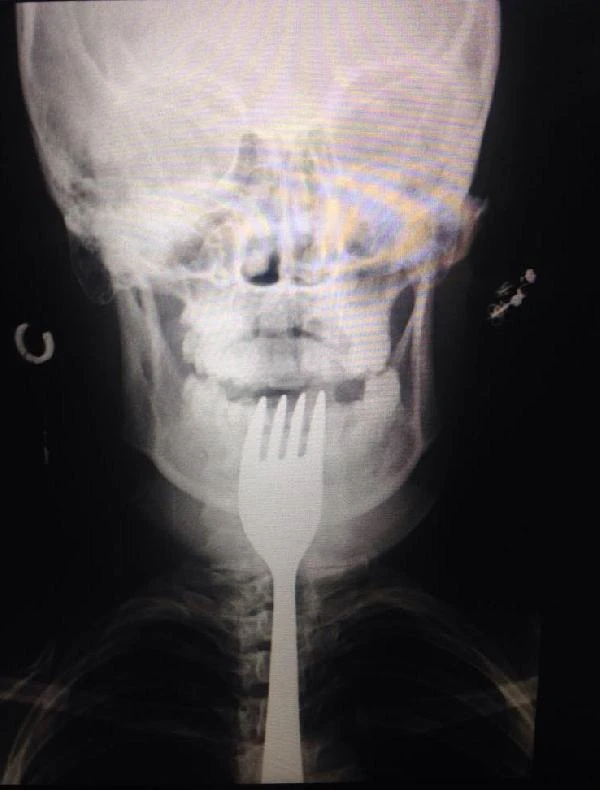

Uludağ Üniversitesi Tıp Fakültesi Hastanesi’ne kaldırılan Naciye Ak’ın boğazına kaçan çatal operasyonla çıkarılırken, genç kızın sağlık durumunun iyi olduğu bildirildi. Olay, dün gece saat 22.30 sıralarında Orhangazi’ye bağlı Üreğil Mahallesi’nde meydana geldi. İddia göre, iftardan sonra çürüyen dişinin arasına giren yiyecek parçalarını çıkarmak isteyen Naciye Ak, çatalla dişini karıştırmaya başladı. Çatal, genç kızın elinden kayarak boğazına girdi. Naciye Ak ailesinden yardım isteyince taksic baba İsmail Hakkı Ak, kızını kendi aracıyla Orhangazi Devlet Hastanesi’ne kaldırdı. Buradaki ilk müdahalenin ardından Uludağ Üniversitesi Tıp Fakültesi Hastanesi’ne kaldırılan genç kızın boğazındaki çatal operasyonla çıkarıldı.

Sağlık durumu iyi olan kızının bugün akşam saatlerinde taburcu edilmesini beklediklerini söyleyen İsmail Hakkı Ak, “İftardan sonra durakta beklerken eşim arayarak, ‘Koş Naciye ölüyor’ diyerek durumu haber verdi. Eve gelip hastaneye götürdüm. Naciye’nin dişlerinden bazıları çürüğü için sürekli şikayet ediyordu. Dişlerini karıştırdığı çatal boğazına kaçmış. Bir türlü doktora götürememiştik” diye konuştu.